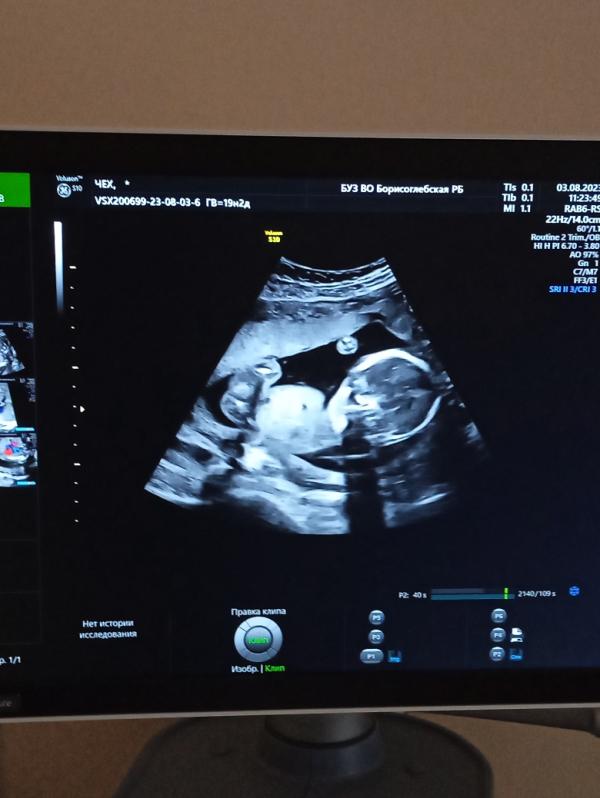

У нас будет.. СЫН💙🤩🥳

Срок 19,2